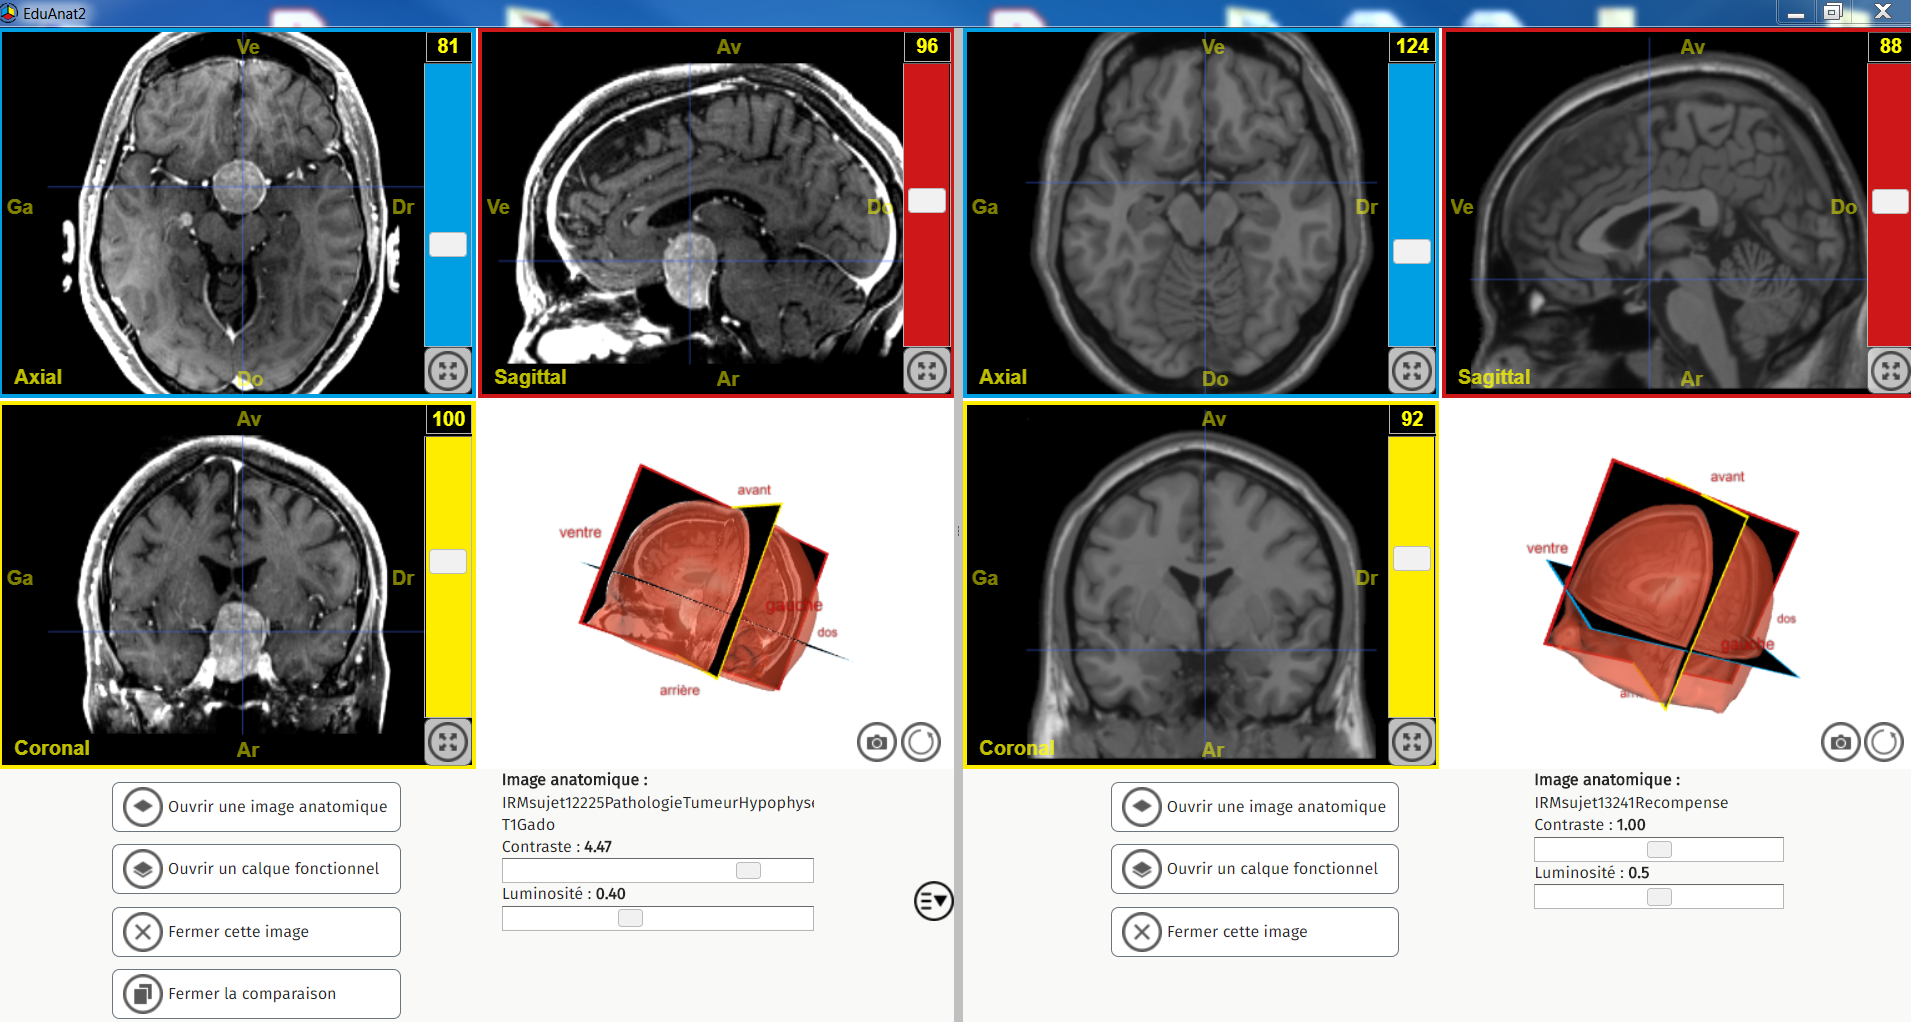

Comparaison Tumeur HypoP et sain

Image dans sa taille originale :

1.13 Mo